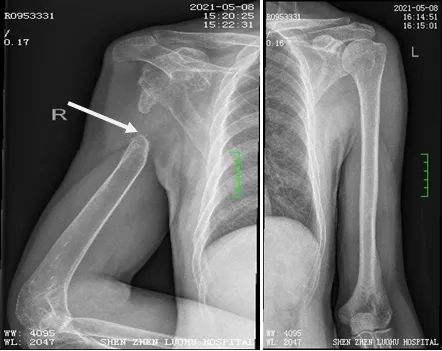

入院后,罗湖区人民医院骨科为宋先生进行了相关检查。经过X线片测量,与左侧正常肱骨对比,右侧肱骨近端缺损长达13cm。

由于宋先生右侧肩关节周围肌肉萎缩严重,软组织条件差,经讨论决定,为其量身定制人工肩关节假体。经过充分的术前准备,杜教授为患者进行了右侧人工全肩关节置换、重建、植骨+左侧髂骨取骨术,手术过程顺利,术后恢复良好。